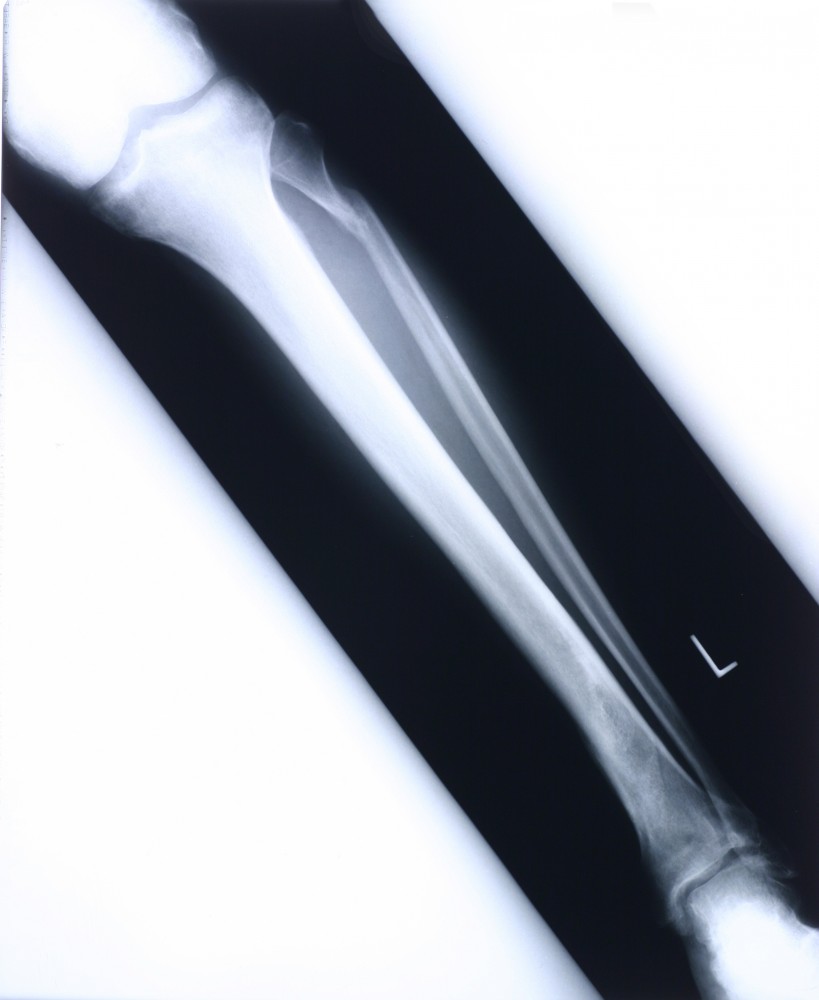

Фото открытого перелома голени

Ниже представлены фотографии открытого перелома голени. Учтите, что изображения могут быть сильно шокирующими и неприятными для просмотра. Если вы не готовы увидеть такие изображения, рекомендуется не продолжать просмотр.